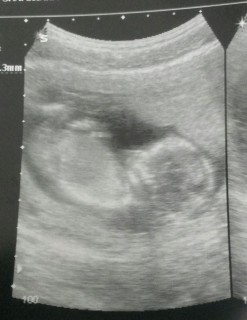

3週間ぶりの検診。大きさも順調だと言われて一安心。短期間でこんなに大きくなっているとは思わなかった(゜o゜)すっかり人間らしい姿になってエコーで見ているときに手をよく動かしていて、おしゃぶりもしてた♬

人間らしくなってきました♪

3週間ぶりの2回目妊婦検診でしたが、とっても大きくなって安心!!2回流産しているので不安はつきまといますが、この子を信じて妊婦生活を楽しみたいです!